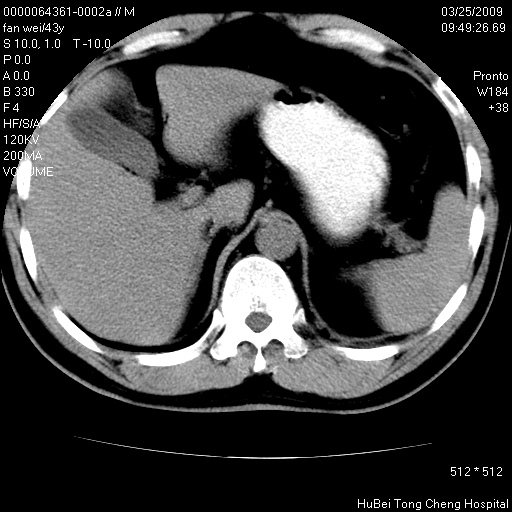

患者 男,43岁。左侧腰部不适两天。平素健康。无家族遗传病史。

腹部彩超提示:1)轻度脂肪肝。2)左肾多发囊性占位性病变;建议行进一步检查。

临床诊断:左肾多发囊性占位性病变,性质待定(多发肾囊肿?)。

双肾ct轴位平扫+增强扫描(层厚10mm,螺距1.0,重建间隔10mm),图像如下: